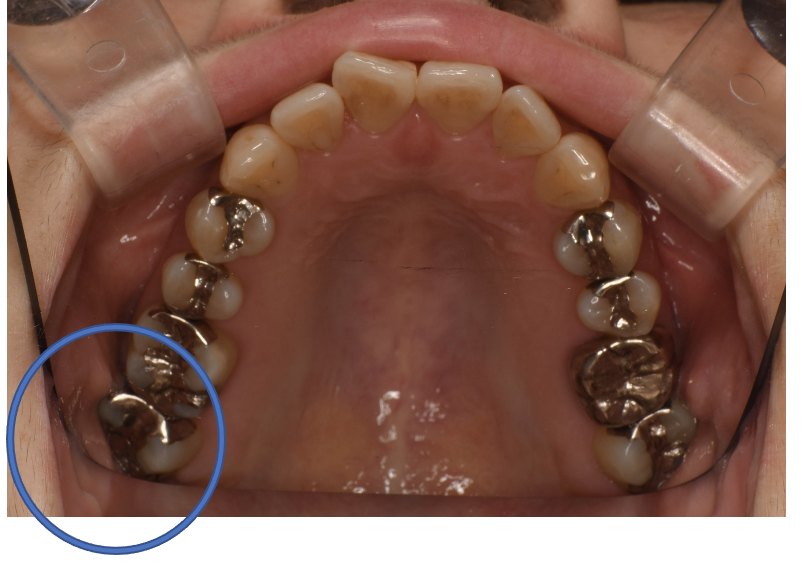

フルジルコニアCr 25 No.56

Before

| 備考 | 院長より 銀歯の内部に虫歯が進行してしまっていたケースです。中を開けて見てみると、外から想像するよりもはるかに虫歯が広がってしまっていました。幸運にも神経を保存できたので、生きた臓器としてまだ使うことが可能です。残存歯質がかなり薄く弱くなってしまったので、ジルコニアで被せて守ってあげています。しっかりとした治療ができたので、まだまだ長く使っていけるでしょう。 |